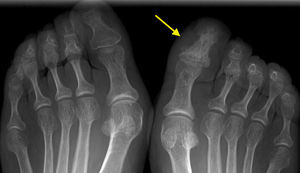

We present the case of a 52-year-old woman with 3-year history of plantar and nail psoriasis. She was referred to us with inflammation and pain in the great toe of her right foot, although she had had no traumatic injury and could describe no general symptoms. Physical examination revealed onychodystrophy, inflammation of the entire toe (dactylitis) and moderate periungual erythema, with no inflammation of other joints (Fig. 1). Acute-phase reactants, rheumatoid factor, anti-citrullinated peptide antibodies and human leukocyte antigen (HLA)-B27 were normal or negative. An ultrasound of the affected area showed an increase in the connective tissue, paratendinitis of the extensor tendon and cortical irregularities in the interphalangeal joint. Plain radiography showed an increase in the entire density of the distal phalanx of the great toe of the right foot, with no significant changes in the interphalangeal joint (Fig. 2).

This radiological finding is referred to as “ivory phalanx”, and is a characteristic sign, but not very widely known in psoriatic arthritis. It is related to periosteum and endosteum condensation with trabecular thickening, leading to a homogeneous increase in the radiological density of the phalanx, giving it an image of global sclerosis that reminds us of ivory.2 It occurs most often in the distal phalanx of the great toes; it can be bilateral and can even effect other toes. It is normally associated with local changes in the nail, and can develop in the earliest phases of the disease.3,4